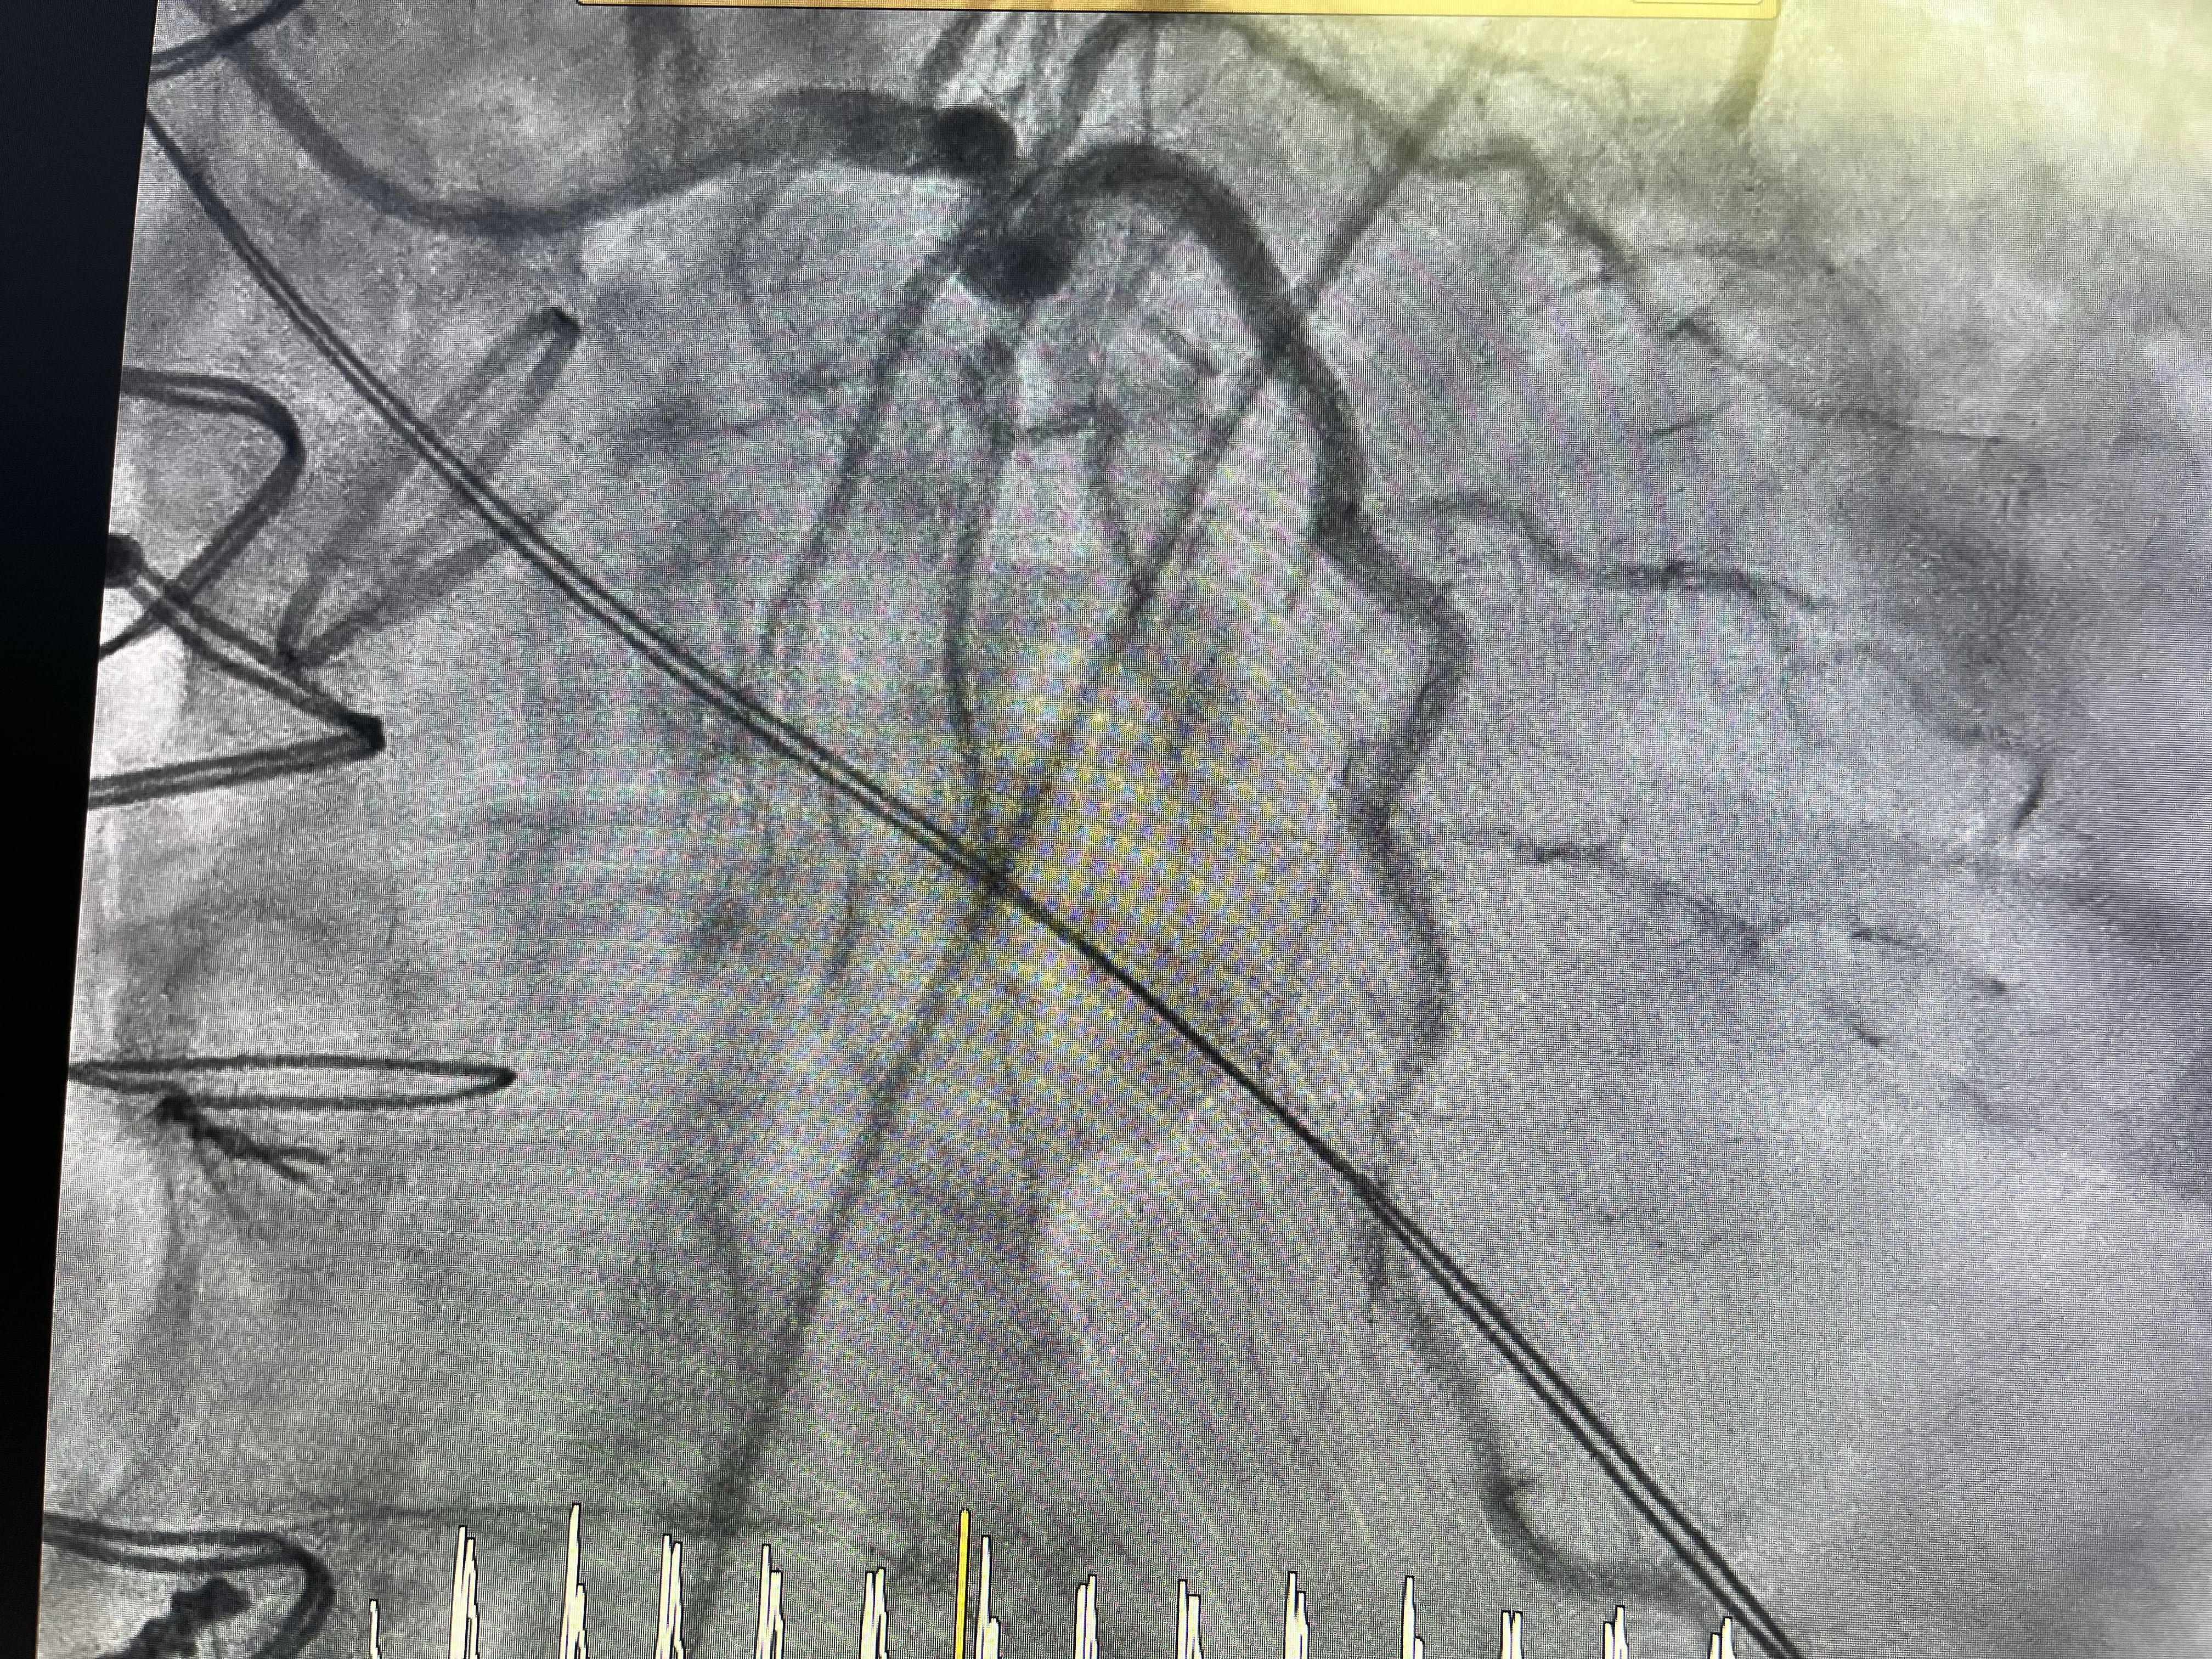

Durante el cateterismo, el objetivo principal es visualizar el árbol coronario y localizar la causa de la elevación del ST. Al inyectar contraste y analizar las imágenes, se hace evidente que la arteria circunfleja está ocluida. La sorpresa, aunque coherente con la anatomía conocida, es que la oclusión no se debe a una placa aterosclerótica inestable, sino a la propia sutura de la válvula mecánica. En otras palabras, la circunfleja ha sido literalmente suturada y estrangulada durante la fijación de la prótesis valvular.

Este hallazgo explica de forma directa el infarto en territorio inferior y la inestabilidad hemodinámica del paciente. El flujo coronario hacia la zona irrigada por la circunfleja está comprometido de forma crítica, generando isquemia severa. En ese momento, el reto del equipo de hemodinámica es doble: por un lado, confirmar que la causa es mecánica y, por otro, intentar restablecer el flujo a pesar de la presencia de la válvula mecánica. No se trata de una angioplastia convencional, sino de una situación límite condicionada por una complicación quirúrgica.

Aun así, se decide intentar la reapertura de la arteria circunfleja mediante técnicas percutáneas. El cateterismo se convierte entonces en la herramienta terapéutica central para revertir el daño. Este enfoque ilustra cómo, incluso tras una cirugía cardíaca mayor, la hemodinámica intervencionista puede ofrecer una salida a complicaciones graves. El caso real de estenosis circunfleja pasa así de ser un problema puramente quirúrgico a un escenario híbrido donde la colaboración entre cirujanos y hemodinamistas es esencial.

Predilatación y Colocación de Stent

Una vez identificada la oclusión de la circunfleja, el siguiente paso es intentar abrir la arteria con un balón. Se realiza una predilatación cuidadosa, avanzando un balón a través de la zona donde la arteria ha quedado comprometida por la sutura de la válvula mecánica. Esta maniobra busca crear un lumen mínimo que permita restablecer parcialmente el flujo y valorar la respuesta del territorio distal. Es un momento crítico, porque se está actuando en una zona anatómicamente compleja y recientemente manipulada quirúrgicamente.

Tras la predilatación, se observa una mejoría en el paso de contraste, lo que indica que la arteria puede mantenerse abierta si se le da un soporte estructural. En ese punto se decide implantar un stent en la circunfleja, con el objetivo de mantener el vaso expandido y evitar una nueva oclusión. La colocación del stent en este contexto no solo trata una estenosis, sino que compensa el efecto de la sutura que había estrangulado la arteria. Es una solución percutánea a una complicación mecánica generada en quirófano.

El resultado de la angioplastia con predilatación y stent es la recuperación del flujo coronario hacia el territorio de la circunfleja. Con ello, se espera que la isquemia disminuya y que la situación hemodinámica del paciente mejore progresivamente. Este desenlace muestra cómo, incluso en un caso tan complejo, la combinación de cirugía cardíaca y cardiología intervencionista puede rescatar una situación crítica. El caso real de estenosis circunfleja queda así resuelto desde el punto de vista coronario, aunque el impacto del infarto dependerá del tiempo de isquemia y de la reserva miocárdica previa.